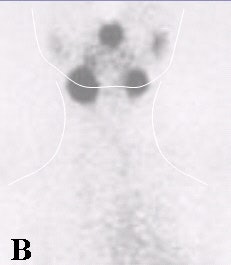

![]() |

| Fifty-three-year-old male with papillary carcinoma who underwent total thyroidectomy. First post-operative scan with 5 mCi 131I at 72 hours. Two foci of remnant metastases are seen. |

| Four weeks later, a scan with 100 mCi 131I at 72 hours was obtained. The stunned lesions failed to take up any of the therapy dose. |

| At one-year follow-up on 5 mCi 131I scan at 72 hours, the same two lesions are present. Images courtesy of Dr. Hee Myung Park. |